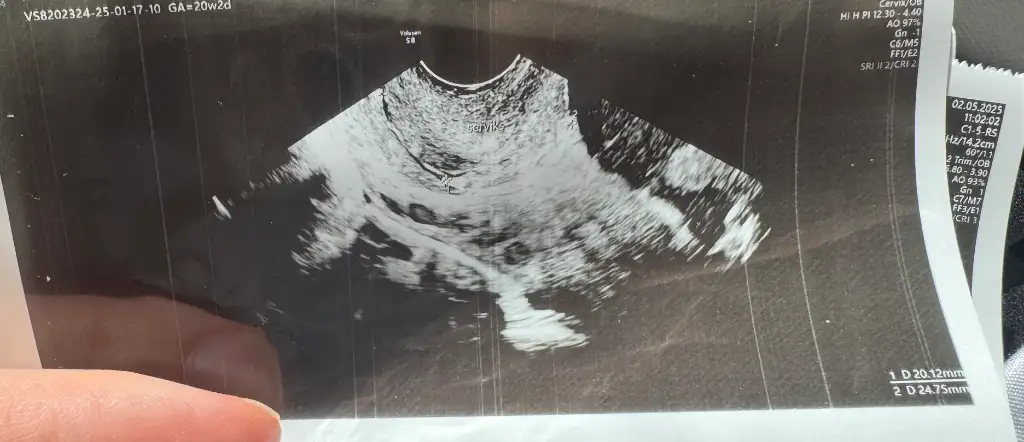

Aa sizinle plasenta konusunda konuşmuştuk bugün yine bir gelişme oldu 🫠🫠 20+2 günlüğüz doktorumuz ilk kes rahim ağzı uzunluğunu ölçtü normal olduğunu plasentanında biraz daha yuksrı çıktığını söyledi plasenta şu an rahim ağzından 2cm yukarda yatmaya devam yukarı çıkıcak inşallah dedide doktordan geldikten sonra ultrason kağıdında rahim ağzı uzunluğumun 20mm olduğu yazıyo herkes sınırın 25mm olduğunu yazmış yine endişelenmeye başladım ya

İnanın plasentanın aşağıda olması bişe bunun kadar risk teşkil etmiyomuş bugün doktorum bile rahim ağzını ölçelim o daha riskli bir durum demişti erken doğumm çok sıkıntı bebeğim daha 20 haftalık 24ü geçicekmi diye çok korkuyorum 😭

Sorun şu ki benimki 20mm sınırın altında ve daha 20 haftalığız neden normal diyip gönderdi hala anlamıyorum ama dikişin riskli olduğunu öğrendim umarım kısa sürede dahafa kısalmaz